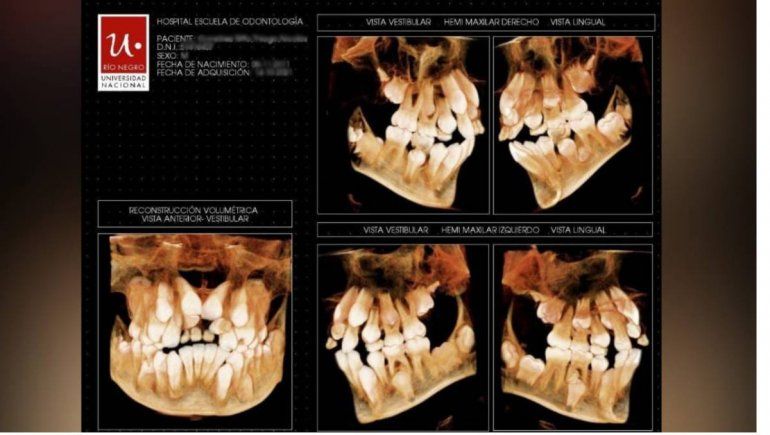

El drama de un nene que tiene ocho dientes de más y dos quistes

Desde hace casi cinco meses que Carmen espera por una cirugía de urgencia para su hijo, de 10 años, a quien no se le cayeron los dientes de leche y tiene ocho piezas de más y dos quistes.

Se dio cuenta del problema al ver que sus dientes de leche no se le caían y comenzaron a salirle los definitivos, por todas partes, en la boca. "Siempre tenía la boca inflamada. Yo no sabía que era por los quistes", acotó.

Las radiografías fueron realizadas por personal del hospital de la Universidad Nacional de Río Negro, totalmente gratuitas.